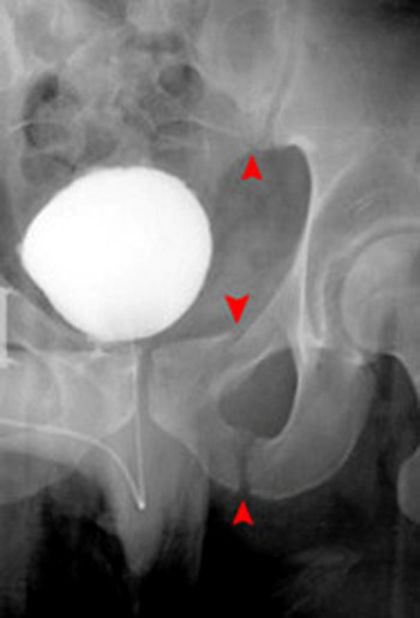

髋关节后脱位

髋关节前脱位